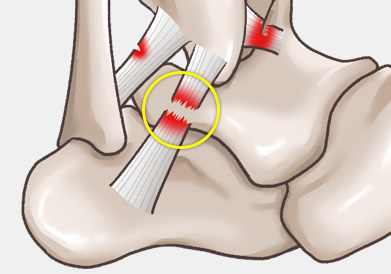

발목 인대 파열은 발목 관절을 지지하는 인대가 외부 충격이나 과도한 움직임으로 인해 늘어나거나 찢어지는 손상을 말합니다.

3도 파열의 경우 인대에 대한 봉합술이 필요합니다.

주로 다음 그림처럼 내반(inversion)에 의해 바깥쪽 인대가 파열되는 경우가 흔하며, 그 중에서도 전거비인대 및 종비인대의 손상 여부가 수술을 결정하는 데 가장 중요합니다.

3도 손상의 경우 전거비인대 완전 파열 뿐만 아니라 종비인대의 손상도 흔히 같이 동반되어 있기 때문에

최소 절개를 통해 micro MBO 수술법을 이용하여 단단하게 인대를 봉합하여 재파열의 가능성을 최소로 낮춥니다.